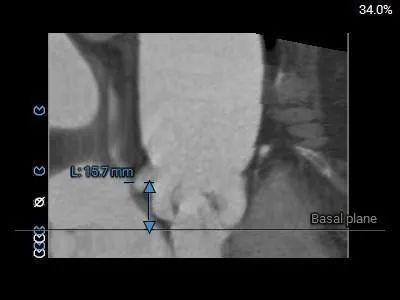

主动脉根部测量:

Type 0型二叶式主动脉瓣,瓣叶增厚,未见明显钙化,交界处未见明显融合